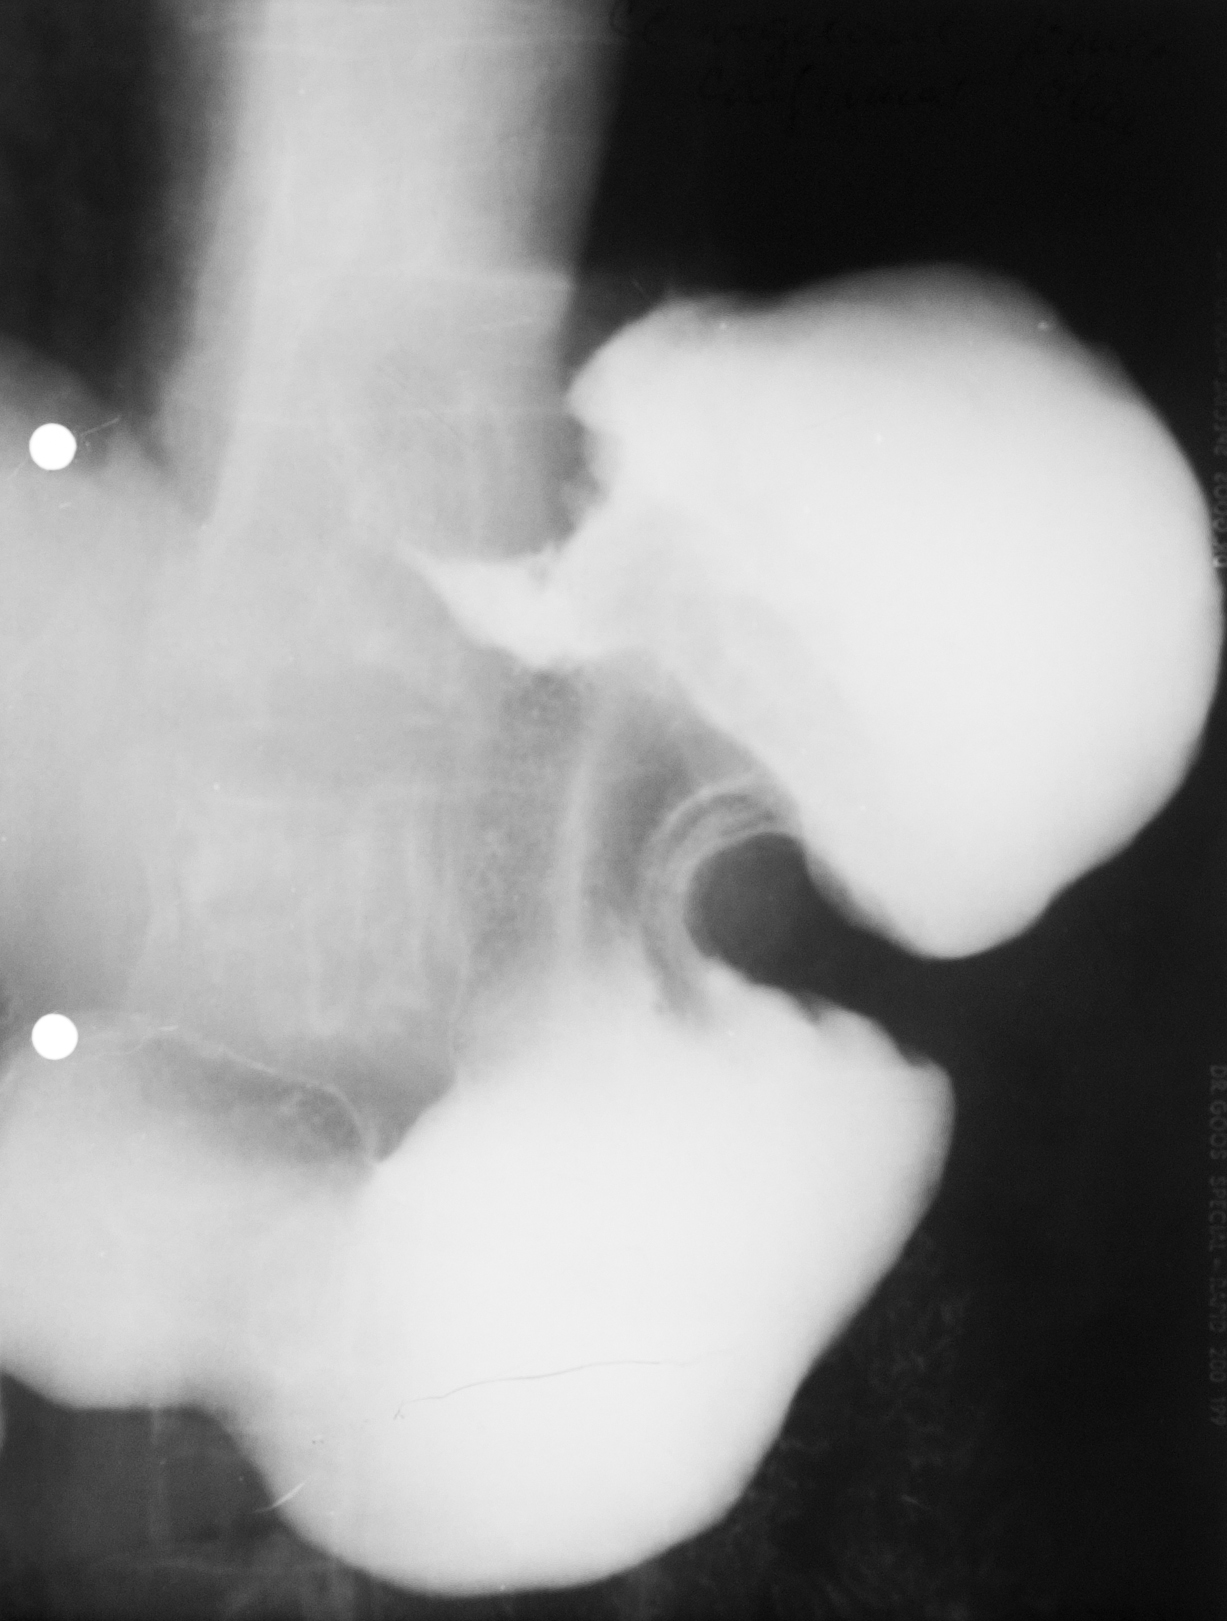

NIȘĂ ÎN LACUNĂ

Examen baritat al corpului gastric

Se observă defecte de umplere,adică dislocuirea substanței de contrast de ceva ce se găsește în lumenul stomacului și anume o masa parenchimatoasă cu contur polilobat.

Cel mai probabil este un proces neoplazic vegetativ de dimensiuni mari,care are la nivelul ei și o ulcerație.Imaginea se numește nișă în lacună.

NIȘA MALIGNĂ ÎN REGIUNEA ANTRALĂ

Nișa malignă este mai mult lată decât adâncă și nu iese din conturul corpului gastric.

Ulcerația este în perete,dar nu iese din conturul peretelui gastric.

ULCERAȚIE CRONICĂ

Se observă,în urma tranzitului baritat,bulbul duodenal cu incizuri la nivelul curburilor,având aspect de treflă,caracteristic pentru ulcerațiile cronice

:NEOPLAZIE INFILTRATIVĂ

Tranzit baritat.Se observă o îngustare semnificativă a lumenului la nivel antral,dând aspect de antru amputat.Nu sunt vizibile pliurile de mucoasă,deci este vorba de o neoplazie infiltrativă.

NIȘĂ LA NIVELUL BULBULUI DUODENAL

Tranzit baritat.La nivelul bulbului duodenal se află o pată persistentă de substanță de contrast,captată la nivelul unei nișe

NIȘĂ DE TIP MALIGN

Nișă de tip malign mai mult lată decât adâncă,situate în regiunea antrală cu pliuri de mucoasă ce converg până în craterul nișei

Tranzit baritat.Bulbul duodenal cu o pată ce persistă pe una din fețele bulbului.Avem de a face cu o nișă de dimensiuni mari la nivelul bulbului

LIMFOM GASTRIC

Imagine lacunară cu contur net linear delimitat,substanța de contrast stă pe această formațiune,înseamnă că există mucoasă gastrică

Proces dezvoltat de la nivelul peretelui,din straturile submucoase

Defect de umplere

DEFECT DE UMPLERE

Defect de umplere. Imagine in monocontrast sus si dublu contrast cele de jos, substanta de constrast este bine lipita de contururile acestui defect de umplere, inseamna ca adera de mucoasa, exista mucoasa gastrica normala.

Într-o formațiune vegetantă carcinomatoasă nu există mucoasă.